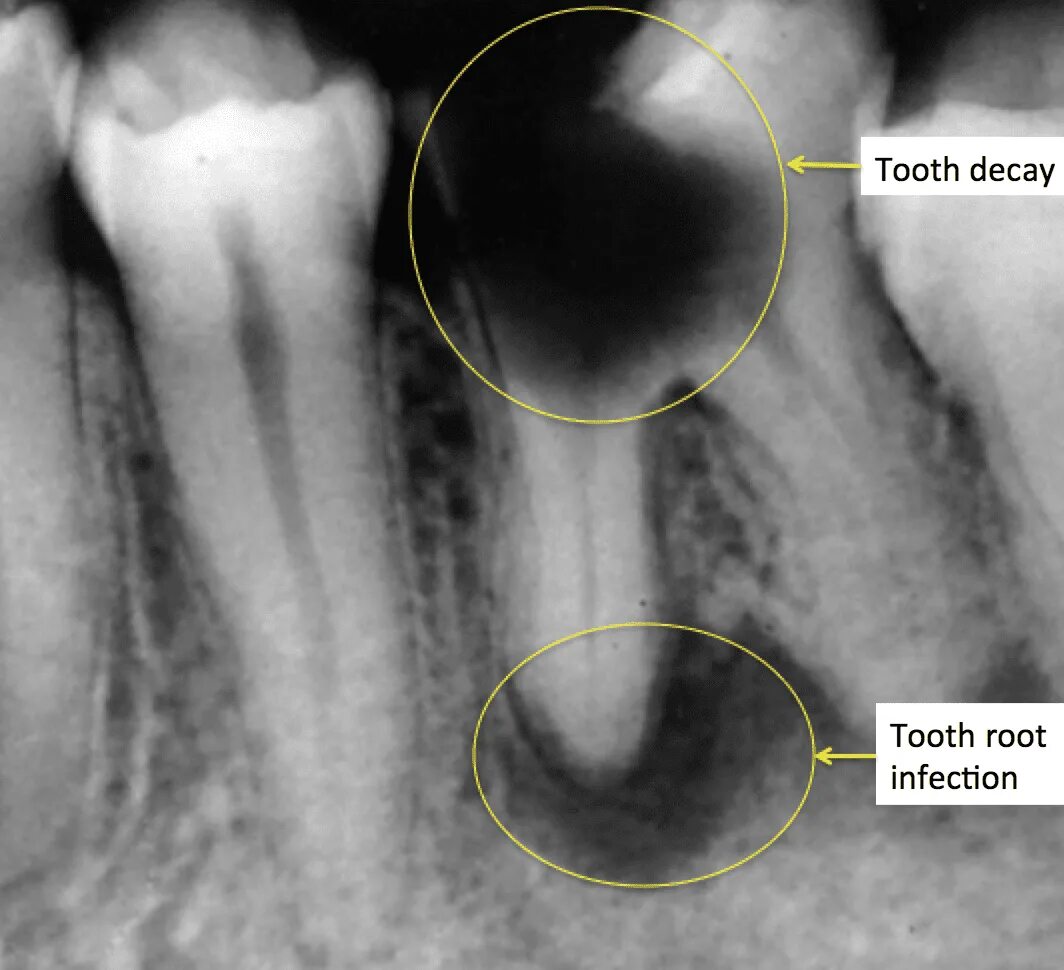

Киста зуба что это